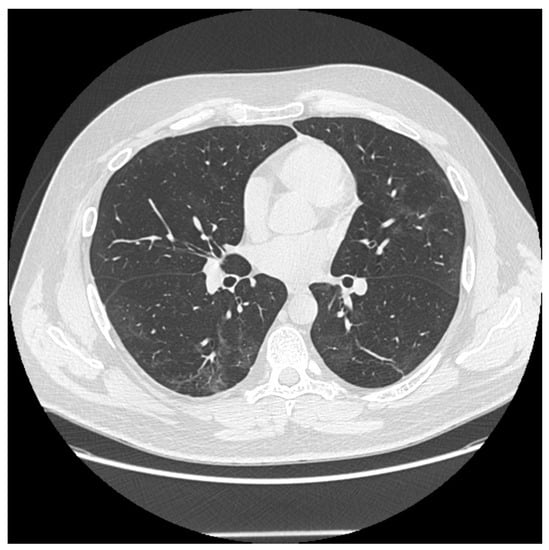

On follow-up CT images, 94.9% of patients still exhibited some persistent radiological abnormalities. The most frequently observed changes at mean 5 months after COVID-19 pneumonia were ground-glass opacities (GGO) (74.4%), reticular pattern (64.1%), fibrotic changes (53.8%) (Figure 1), nodules (33.3%), bronchiectasis (15.4%), vascular enlargement (10.3%), and cavitation or air bubble signs (5.1%) (Figure 2). Table 4 shows the complete distribution of lung abnormalities in both severe and moderate groups, as well as the clinical characteristics of patients. No significant differences were noted between various sex subgroups, nor between the severe and moderate progression of the illness. However, the prevalence of reticular pattern, fibrosis, bronchiectasis, and vascular enlargement was slightly higher in the severe group of patients compared to the moderate group.

Figure 2. Multiple persistent ground glass opacities in a female patient 5 months after the onset of disease with singular cavitations and fibrotic lines.